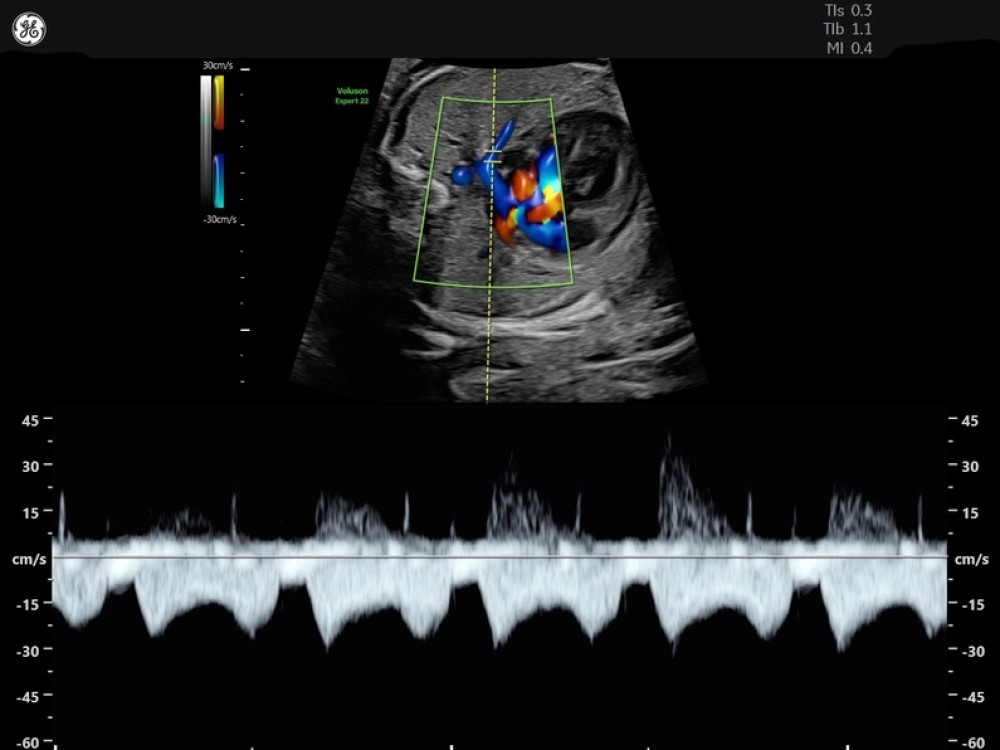

• Voluson Expert 22 real vaxtda yüksək məkan həssaslığına malik görüntülərin əldə olunmasını təmin edən avansert 4D volumetrik görüntüləmə texnologiyasından istifadə edir və bu, klinik diaqnostikanın dəqiqliyini əhəmiyyətli dərəcədə artırır.

• 3D/4D volumetrik görüntüləmə

• Rəngli Doppler

• M-Mode